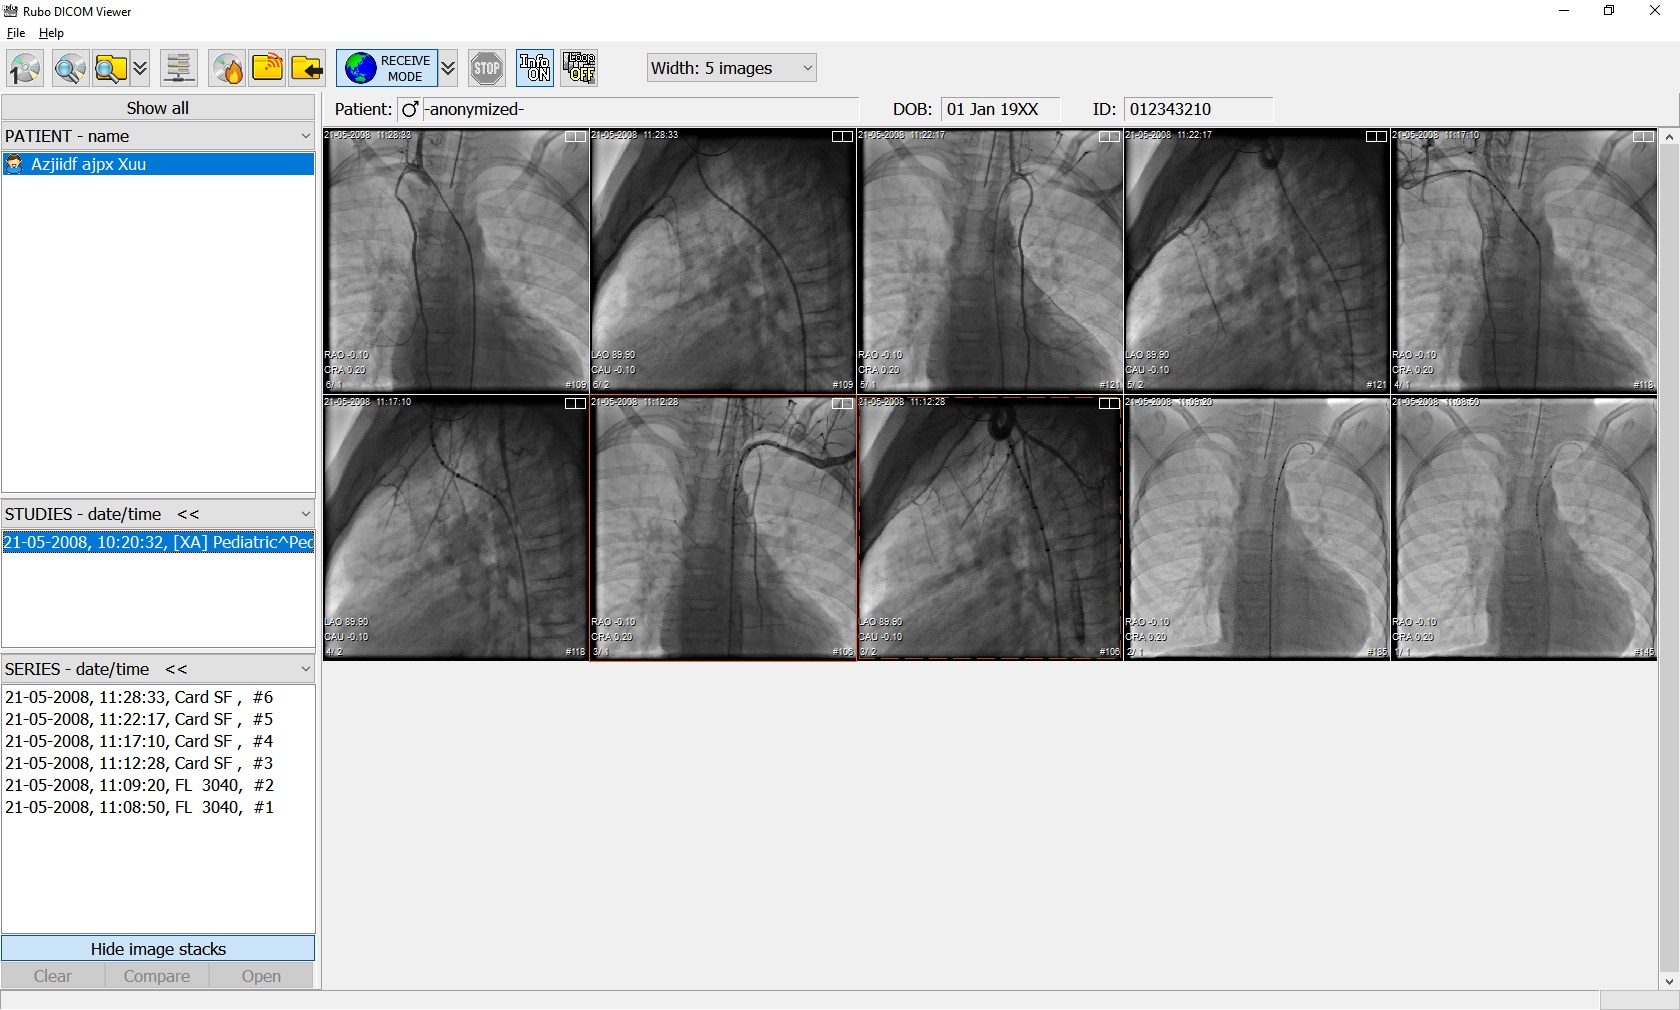

Лазерная камера для печати медицинских изображений на пленке стандарт dicom